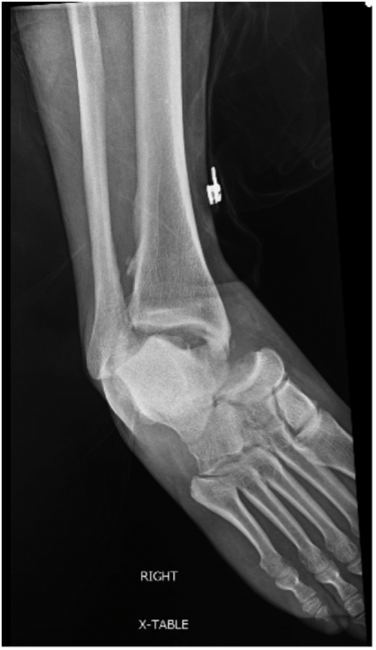

One should obtain plain film radiographs in the emergency department (Figure 1 above) prior to reduction and then following reduction. Multiple postreduction views should confirm proper position of the tibiotalar, subtalar, and talonavicular joints. Following reduction, computerized tomography (CT) scans may assist in identifying any residual intra-articular debris or articular irregularities.6,7 Additionally, one should consider CT results prior to taking the patient to the operative suite. Additionally, 3D-reconstructed CT scans may help scrutinize reduction and aid in surgical planning (Figure 2 below).

At this time, we elected to place an anchor into the distal tip of the fibula to repair the ruptured CFL. We additionally augmented the anterior talofibular ligament (ATFL) with absorbable suture. We then noted clinical stability of the ankle joint, STJ, and TNJ after intraoperative stressing (Figure 5 above).